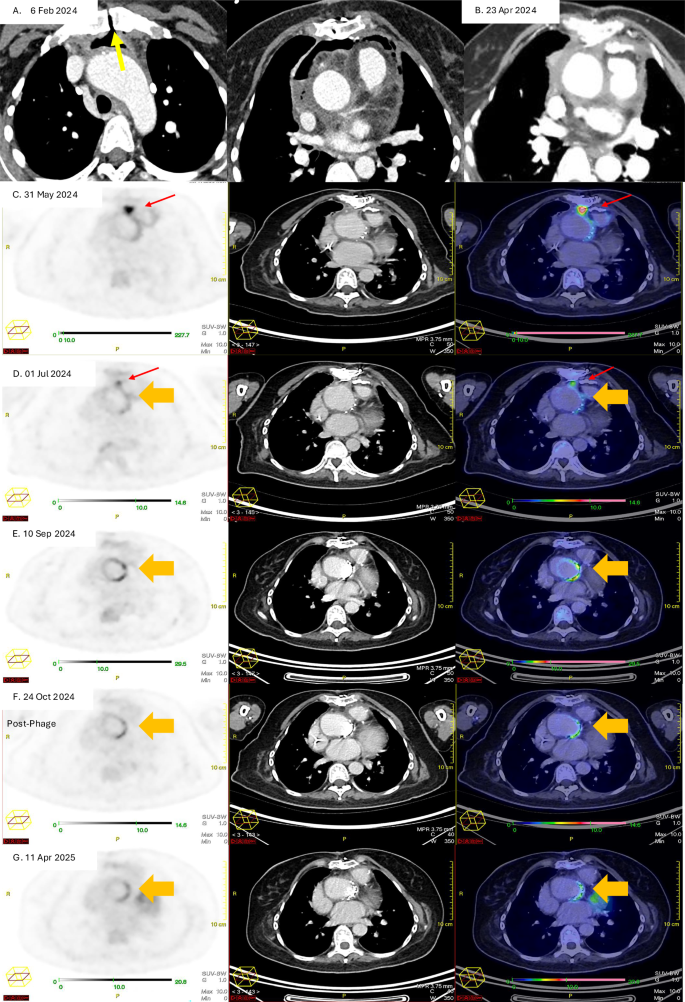

A CT Aortogram (Thorax) on 6 February 2024, following her Bentall procedure, showing heterogeneous anterior mediastinal collection with gas locules surrounding the aortic arch and ascending aorta. There is gas seen tracking through the midline sternotomy (yellow arrow). B CT Aortogram on 23 April 2024 shows resolution of the pneumomediastinum but there is interval development of a hyperdense rind along the ascending aorta and within the anterior mediastinum. C–E Pre-phage therapy attenuation corrected 18F-FDG PET image. CT image and fusion 18F- FDG PET/CT images at different time points in chronological order. There is an initial intense 18-FDG-avid focus of uptake posterior to the sternotomy wire (red arrow). This shows interval decrease in intensity and then subsequent metabolic resolution by 10 September 2024. However, there is serial interval increase in the circumferential 18F-FDG uptake around the aortic valve prosthesis (orange arrow), suggestive of an underlying active infective/inflammatory process. F,G. Post-phage therapy attenuation corrected 18F-FDG PET image. CT image and fusion 18F-FDG PET/CT images at different time points in chronological order. The most intense tracer uptake around the graft was seen in September 2024, and following phage therapy, there is interval sustained improvement following the administration of phage therapy showing interval decrease intensity of the circumferential 18F-FDG uptake along the aortic valve prosthesis (orange arrow).

The decision to pursue adjunctive salvage phage therapy was driven by her clinical course and serial 18F-fluorodeoxyglucose positron emission tomography/computed tomography (18F-FDG PET/CT) findings, which showed persistent tracer uptake in the aortic graft despite prolonged high-dose combination antibiotic therapy guided by TDM. However, the risk of relapse once antibiotics were discontinued was concerning. (See Fig. 2.) In addition, there were interval development of vascular access complications: Vascular catheter exit site infection developed on September 4, 2024, necessitating line replacement; long term intravenous antibiotic therapy was not tenable. Definitive surgery to remove the composite vascular graft was technically challenging with high operative risks, significant morbidity and mortality, which was unacceptable to the patient. Phage therapy offered the possibility of restoring antibiotic susceptibility to fluoroquinolones and beta-lactams with the aim to suppress the VGI. Approval for the use of investigational phage therapy was obtained from our hospital medical ethics committee. The patient was also counselled, and she later consented to receiving phage-antibiotic combination therapy as part of salvage treatment.

The patient was symptom free before and after phage therapy with no impairment in daily activities. The most significant observation following phage administration was the reduction in tracer uptake around the prosthetic aortic valve 1 and 2 months after phage therapy on serial 18F-FDG PET/CT (Fig. 2F). The serial CRP and ESR readings also returned to normal limits 15 days, and 85 days post phage therapy, respectively. Intravenous piperacillin-tazobactam was discontinued on December 3, 2024, and the central venous catheter was removed. The patient was subsequently maintained on levofloxacin monotherapy with no recurrence of bacteremia.